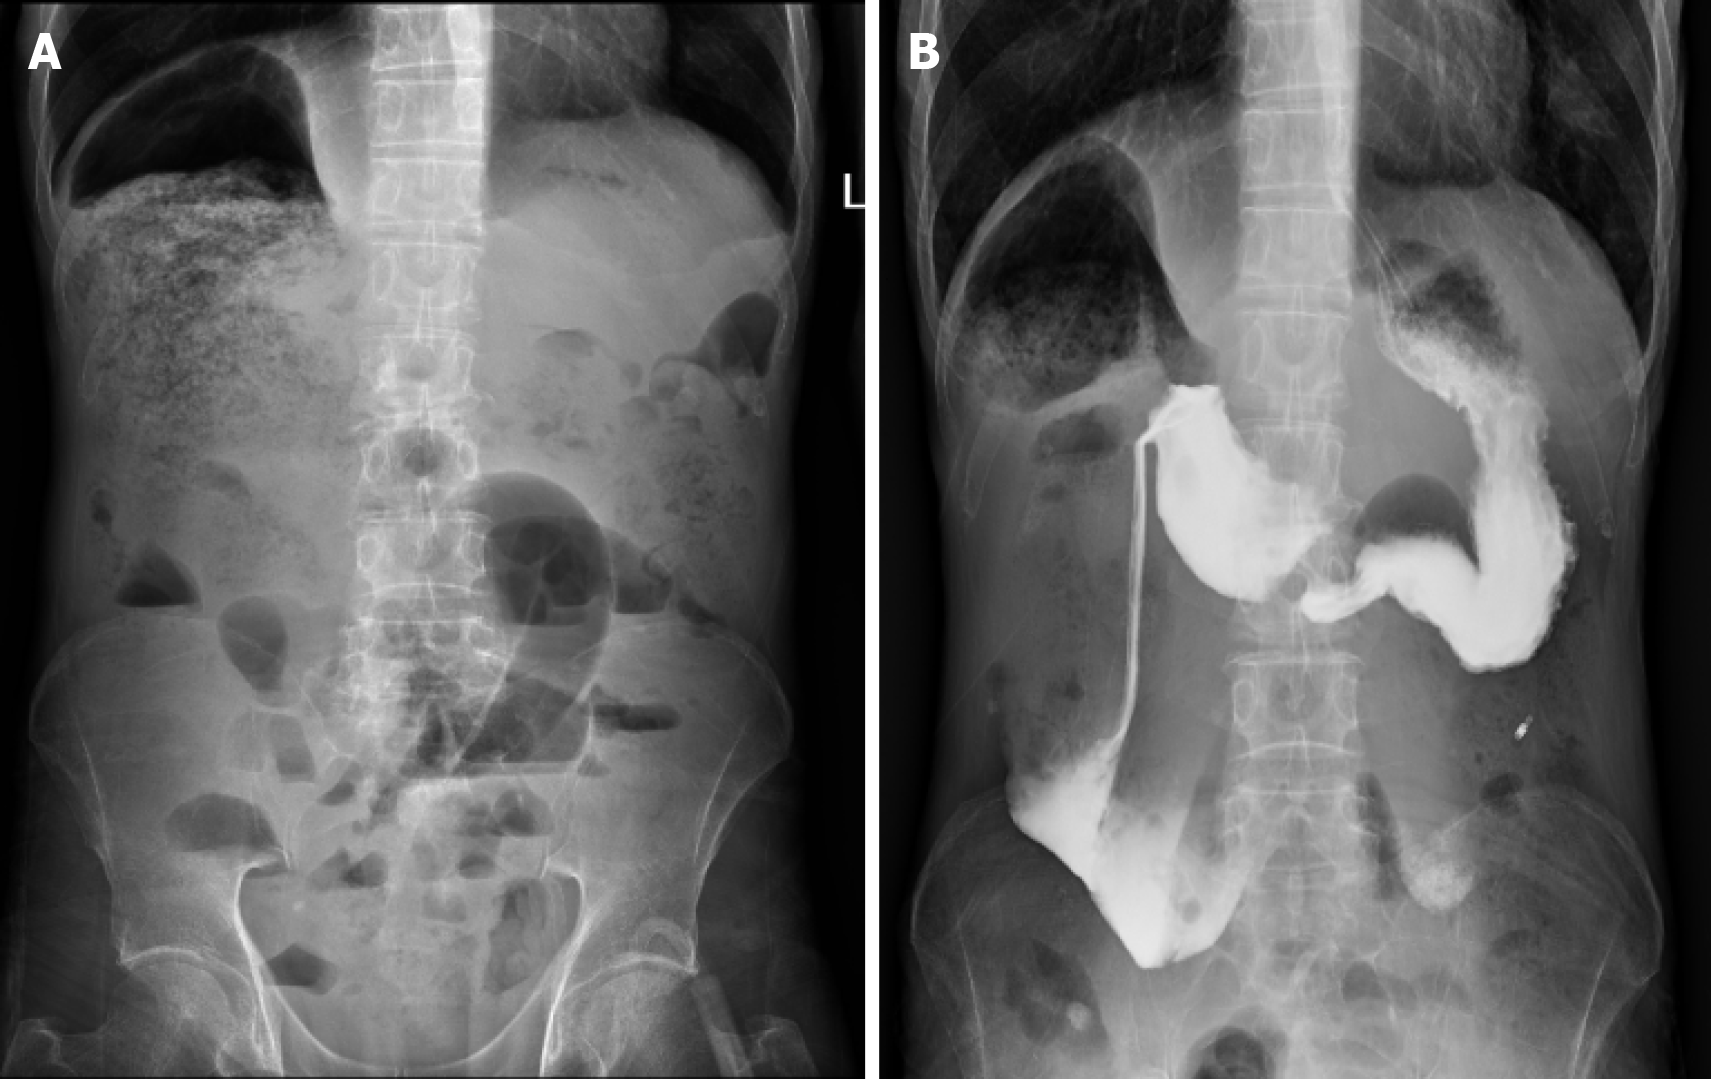

Renal ultrasonography revealed dilation of the left renal collecting system with mild upper ureteral dilatation. Abdominal radiography (Figure 1A) showed right hemidiaphragm elevation and dilated bowel loops with air-fluid levels. The findings of the upper gastrointestinal barium study (Figure 1B) demonstrated mild esophageal dilation, as well as marked duodenal bulb and descending segment dilation with contrast retention. Abdominal CT (Figure 2) revealed duodenal sac-like dilatation with positional changes, narrowing of the horizontal segment, segmental jejunal dilatation, reduced bladder tone, and an indwelling urinary catheter. Abdominal magnetic resonance imaging (Figure 3) revealed significant duodenal and multiple small intestinal dilatations. Gastroscopy revealed reflux esophagitis (LA-B), gastric retention and deformation, and duodenal dilatation with villous atrophy. Colonoscopy revealed a polyp located in the descending colon, which showed an unremarkable anastomotic site.